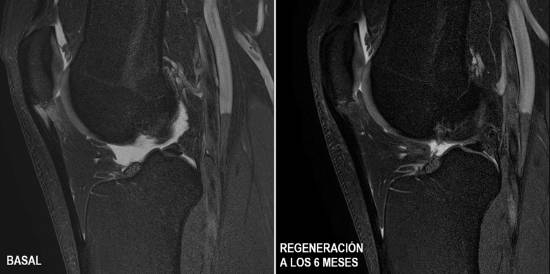

Per demostrar-ho es va realitzar un assaig clínic a doble cec, comparant dos grups de pacients, un tractat amb PRP (Plasma Ric en Plaquetes) i l'altre amb CMMC. El grup tractat amb PRP no va mostrar evolució alguna, mentre que els tractats amb CMMC van obtenir un grau de regeneració de l'estructura del tendó sense precedents en el 100% dels pacients, amb reincorporació a la pràctica esportiva als 2 mesos.

Al llarg dels últims 20 anys, ITRT ha aportat evidència científica i ha demostrat en assaigs clínics que es pot crear teixit nou en qualsevol tendó i recuperar la lesió com si mai hagués succeït. Durant aquest temps, el centre ha tractat a gairebé 150 pacients de lesions, entre ells esportistes d’elit a nivell mundial, de tots els tendons: des del rotulià, el d'Aquil·les, l’isqui tibial o el supraespinós...